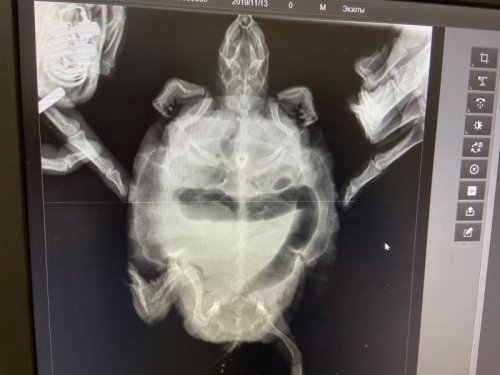

Ростовская область, г. Белая Калитва. Красноухая черепаха найдена в речке в сентябре. Аквариум на 50 литров, фильтр для очистки воды, термометр, водонагреватель. Температура в воде 34.  Лампа дневного света стоит выше стекла, горит 12 часов днем, ультрафиолетовой лампы нет. Установлен стеклянный остров для черепахи с искусственным газоном, с дорожкой до самого дна нет в городе большого. Фильтр внутренний для воды. Грунта нет, еще ничего нет. Все приобретено срочно, так как опыта содержания нет, а ей нужно тепло как сказали. Ест раз в 4 дня 1 креветку, мотыль не ест, одуванчик не ест, сухой корм не ест никакой. Вес 550 гр с панцирем. Крупная, сейчас на работе размер точный не скажу. Черепаха появилась почти месяц назад, кололи 5 дней антибиотик в больнице, глаза закрыты и трещина на панцире. делаем ромашковые ванны, мажем глаза тетрациклином на ночь, гидрокартизоловой мазью днем и левомицитиновые капли. Глаза то откроются то закроются опять, лапы сильные стали. но когда плавает задними не пользуется и на островок залезть не может. Фото сделано почти в начале, сейчас глазки получше. Есть у нас шанс выжить? Кто то видимо в речку выкинул летом, авось выживет... Что делать скажите пожалуйста, специалистов в этой области нет у нас. Доктор которая колола говорила что антибиотик для черепах подходит. рентген не делали, ездили на укол в контейнере, мне кажется это стресс большой для животного.